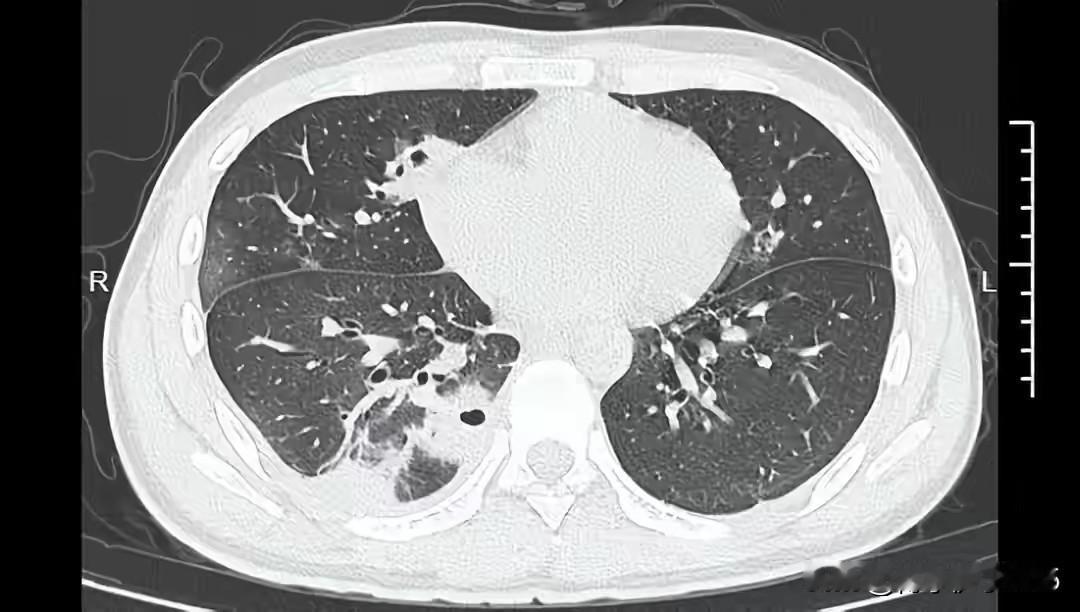

宁波20岁男生挤了1颗痘痘,挤进了ICU!肺里密密麻麻 这位宁波20岁的年轻小伙子,原本只是为了摆脱一颗烦人的痘痘,却没想到一场小小的“挤痘行动”竟让他付出了沉重的代价。事情的经过令人震惊,也让人不禁反思:我们对健康的忽视,究竟埋藏着多大的风险? 事情发生在一个普通的周末,年轻人因为脸上的一颗痘痘,心生烦躁,便用手挤了几下。谁曾想,这个看似微不足道的动作,却成为了他生命的转折点。几天后,他开始出现咳嗽、发热,症状逐渐加重,最终被送往医院。检查结果令人震惊——他的肺部密密麻麻布满了细菌和脓液,诊断为“严重的肺部感染”,医生不得不将他送入ICU,进行紧急治疗。 这起事件让人不禁心头一紧。挤痘痘看似简单的小事,实际上隐藏着巨大的健康隐患。皮肤上的痘痘,虽然看起来微不足道,但如果不注意卫生或用力过猛,极易引发细菌感染。尤其是在免疫力较低或身体状况不佳时,一次轻率的挤压,可能引起细菌逆行感染,甚至危及生命。 更令人担忧的是,很多年轻人对健康知识的缺乏,抱着“忍一忍就过去了”的心态,忽视了身体发出的警示信号。其实,身体的任何不适都不应被忽视,尤其是感染性疾病,一旦扩散,后果可能比想象中严重得多。我们常说“健康是最大的财富”,但在日常生活中,多少人为了所谓的“美丽”或“方便”,忽略了最基本的卫生与健康常识。 这起事件也提醒我们,面对生活中的小细节,要有更科学、更理性的态度。不要为了短暂的舒适,冒险触碰身体的“底线”。更重要的是,要学会倾听身体的声音,遇到异常症状时,及时就医,而不是自己“忍一忍”或随意处理。 此外,社会也应加强健康教育的普及,让年轻人了解皮肤护理的正确方式,认识到“挤痘痘”背后潜藏的风险。健康,从细节做起,每一个小习惯都关系到生命的质量。我们希望,这个年轻的生命不会因为一颗痘痘而付出沉重的代价,也希望每个人都能从中吸取教训,重视自己的健康。 生命如此脆弱,却又如此坚韧。只要我们多一份细心和警觉,就能远离那些看似微不足道,却可能引发巨大危机的小事。愿这个年轻人早日康复,也愿我们每个人都能用科学和理智守护自己的健康,让生命在平凡中绽放出不平凡的光彩。痘痘 粉刺爆痘 解压挤痘痘 挤痘后遗症 健康 生命